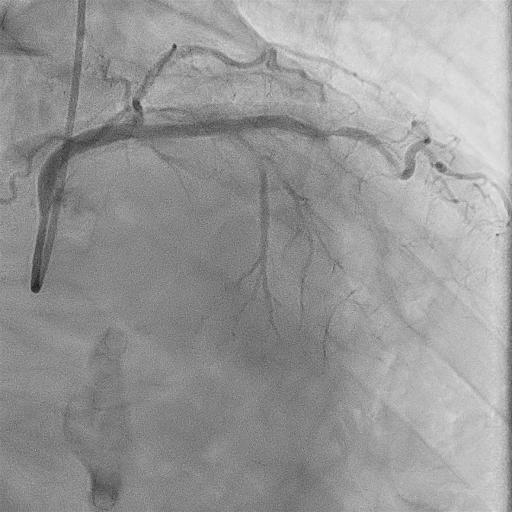

Relevant Catheterization Findings

The left coronary artery had a severely calcified CTO from LAD segment 7, with no interventional collaterals, including from the right coronary artery.

The procedure began via right and left femoral arteries using Launcher 8F EBU3.5SH and 7F SAL0.75SH guiding catheters. Zizai 150 cm and Corsair Pro 135 cm microcatheters were used. An antegrade approach with wire escalation from SION to XT-A and Conquest Pro 8-20 was attempted. SION and a 2.5¡¿15 mm Ryurei balloon were used as anchors, but a heavily calcified ¡°full moon-like¡± distal LAD lesion could not be crossed. GUIDEPLUS 5F with a 2.5¡¿15 mm Ryurei enabled guide extension lock, though attempts with Ryurei 1.0¡¿5 mm and Mogul SP Thinner 1.5F failed. Using SASUKE 145 cm, Gladius EX was redirected into the subintimal space via Corsair Pro and a 2.25¡¿15 mm Ryurei. ELCA (0.9 mm) and PTCRA with FINECROSS MG and Mogul SP Thinner were unsuccessful as the RotaWire could not cross. Subsequent ballooning with Ryurei 2.25¡¿15 mm and Hiryu Plus 2.5 mm was performed. ADR using Caravel MC and Conquest Pro 12ST achieved true lumen re-entry, followed by stenting with GUIDEPLUS II ST 6F and DESs.